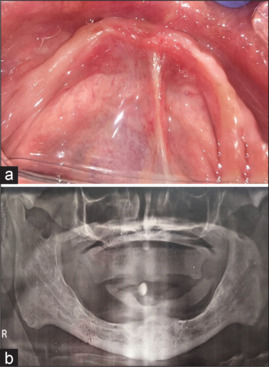

Materials and methods: The bone with respect to IAC in 60 sites from 10 patients was assessed on both sides of the atrophic mandible. Measurements were taken at 10 mm, 20 mm, and 30 mm from the mesial aspect of the retromolar pad. After assessment, 20 implants were placed bypassing IAC in five patients, and postoperatively, neurosensitivity test was performed. Descriptive analysis was used to compare the different measurements from the retromolar pad on the right and left sides. Unpaired 't' test was used. A P value less than 0.05 was considered as statistically significant.

Conclusions: Dental implants were placed successfully in the atrophic mandible, bypassing the IAC. IAC is placed more lingually toward the medial border of the retromolar pad and then becomes buccally in the premolar region. Buccal bypass is safer and easier than lingual bypass due to the lingual position of IAC.